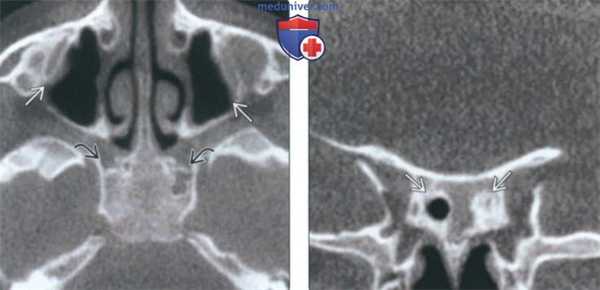

(Слева) На аксиальной КЛКТ справа и слева визуализируются добавочные устья ниже уровня соответствующих крючковидных отростков. Основные устья находятся на другом уровне и не видны на этом срезе.

(Справа) На корональной КЛКТ у этого же пациента визуализируются дополнительные устья справа и слева. Основные устья на этом срезе не видны. Обратите внимание на субтотальное снижение пневматизаци левой верхнечелюстной пазухи.